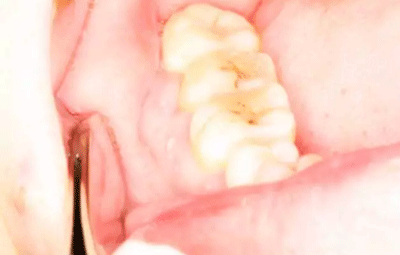

圖3.術(shù)前口內(nèi)影像情況:48頰側(cè)牙齦紅腫。照片有點(diǎn)曝光過(guò)度。不理想。